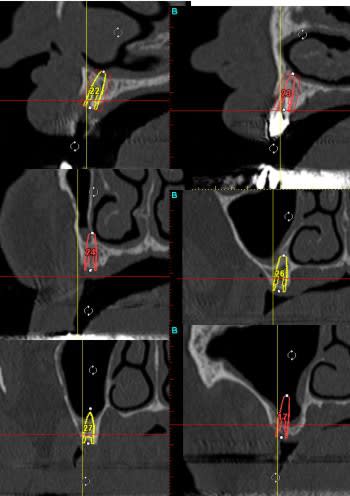

Voici le scan:

Feyimg 8735 c2cykn - Eugenol

Feyimg 8733 kvghzr - Eugenol

Feyimg 8734 fc50c4 - Eugenol

03/11/2009 à 16h01

dommage qu'on voit pas ce qu'il y a dans les coupes 50/60...

sinon, c'est une autoroute....là un "all on" 5 ou 6 implants...çà le ferait bien...;-))

Voilà voilà

Feyimg 8742 sgd7sv - Eugenol

03/11/2009 à 17h44

je confirme...autoroute...

j'aimerais bien en avoir des comme çà tous les jours à mon cab...;-))

tu poses les implants gribouille???

si oui...fais une étude pré-prothétique et implantaire à posit...et là c'est sur du velours...

je ne vois pas ça comme un boulevard.

si j'ai bien compris il y a déja eu 1 implant avec perimplantite.

je n'ai pas une vision d'un os en parfaite santé, mais le scan n'est pas suffisant, le bilan bio donne quoi?

heu...j'ai peut être pas très bien chaussé mes lunettes pxav...mais les repères sous les coupes...si on s'en réfère à la mesure de référence donnée tout à droite de la dernière planche de scan( "règle" de 10cm)...semblent être des repères de plan de coupe de 2mm...

mis à part dans la zone des incisives où là c'est plus étroit (normal)...à partir des canines, on a des crêtes d'au moins 6/8 mm minimun....

peut être que gribouille pourrait confirmer...mais si c'est le cas...je sais pas ce qu'il te faut pour planter....

par contre, d'accord avec toi pour la qualité, ou santé osseuse...il faut peut-être être assez prudent sur ce cas